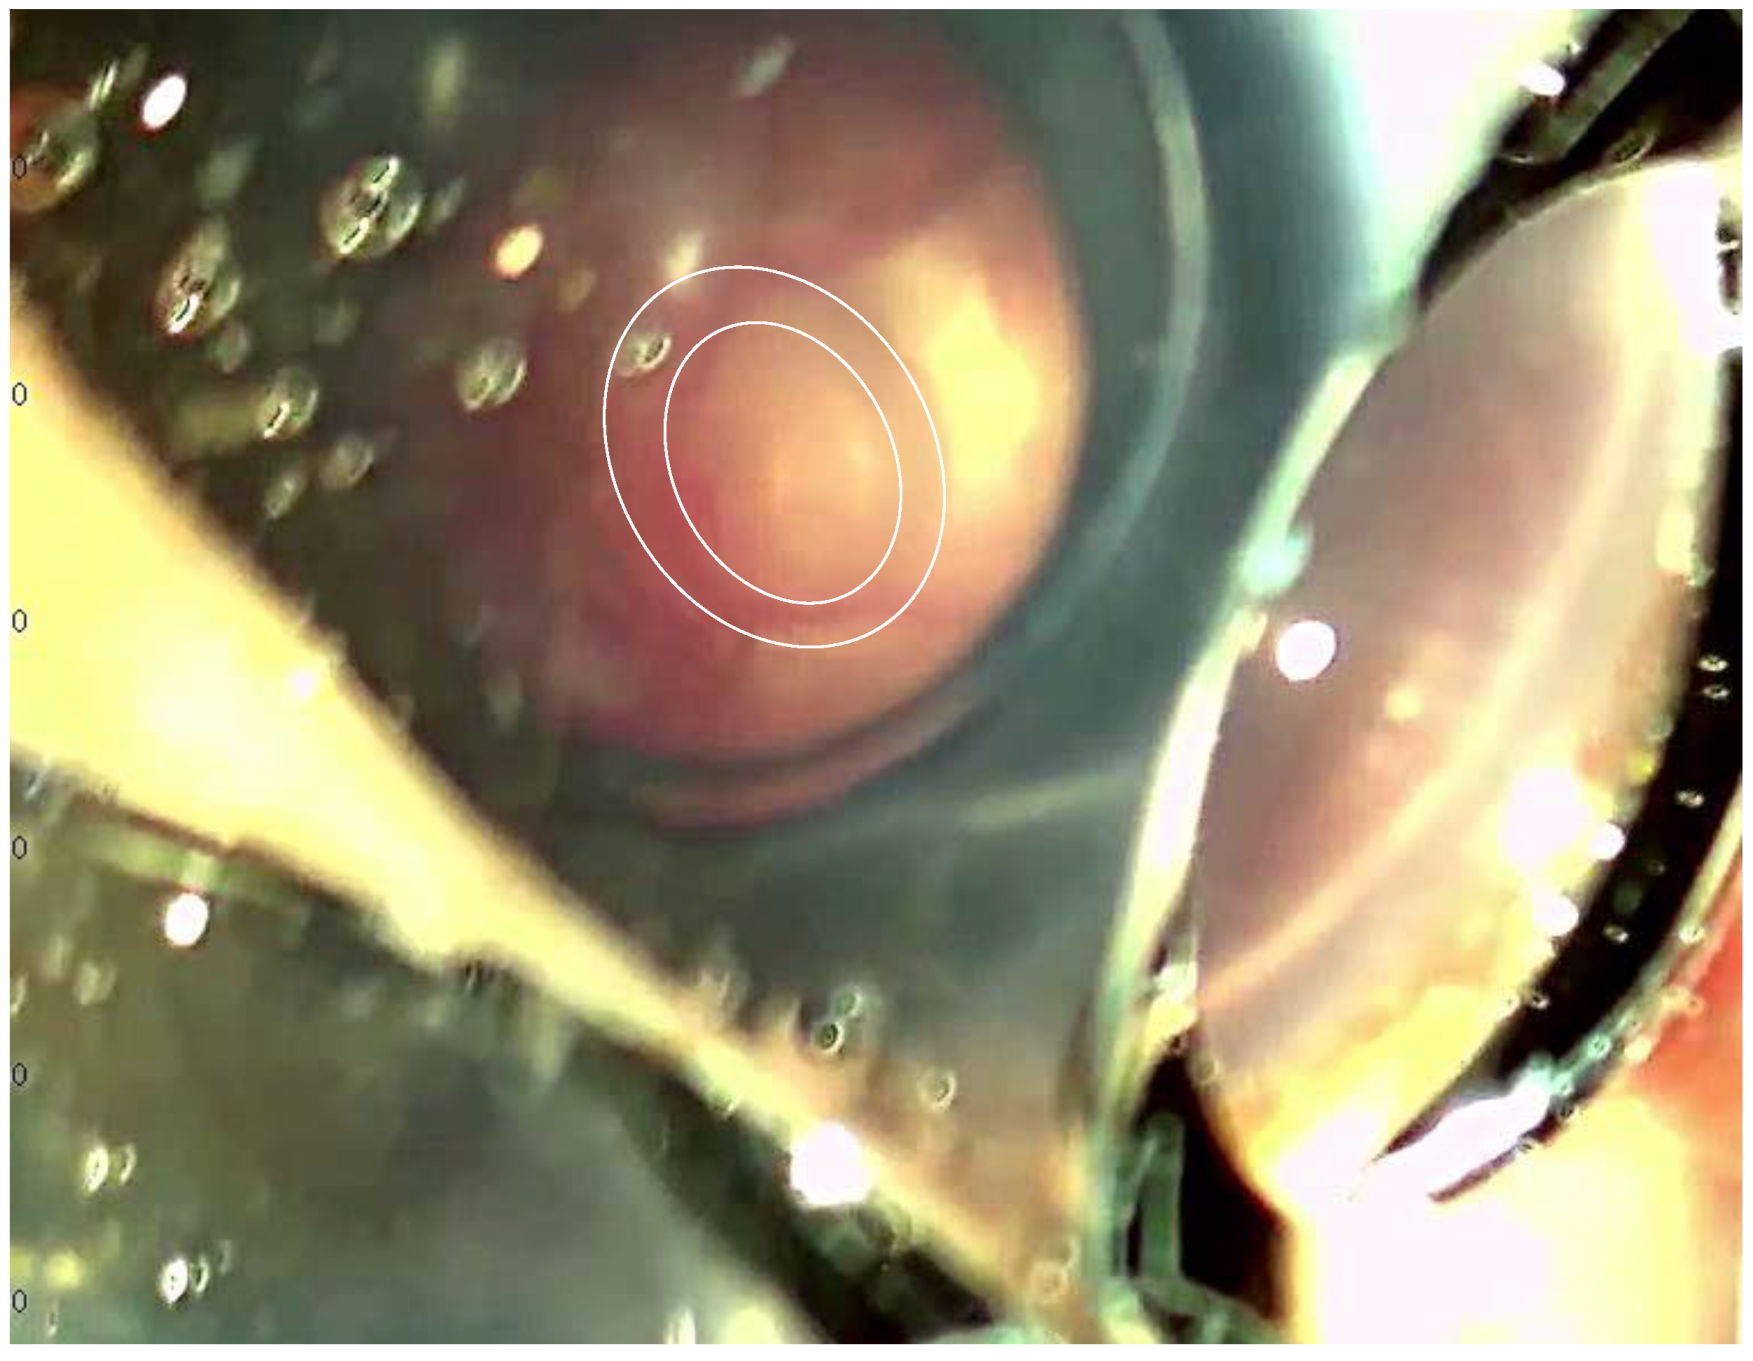

2. Case Report